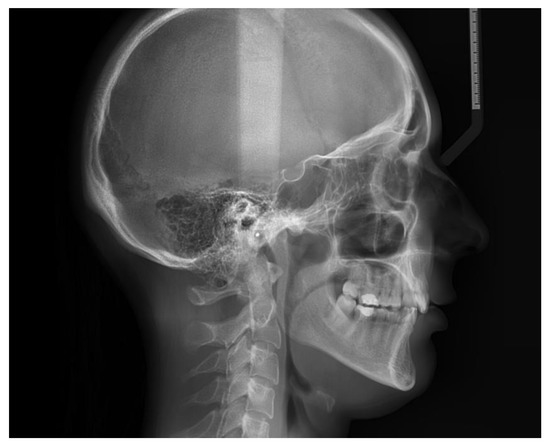

| SNA | 80.03 | 81.08 | 3.7 | Normal A-P position of the maxilla |

| SNB | 75.40 | 79.17 | 3.8 | Normal A-P position of the mandible |

| ANB | 2.46 | 4.63 | 1.8 | skeletal class II |

| FMA | 26.32 | 29.63 | 3.0 | Hypodivergent facial pattern |

| Gonial angle | 123.44 | 124.31 | 5.4 | Normal gonial angle |

| APDI | 74.22 | 85.74 | 4.0 | Skeletal class II |

| A to N-Perp (FH) | −2.58 | 0.4 | 2.3 | Retruded maxilla |

| B to N-Perp (FH) | −12.06 | −3.5 | 2.0 | Retruded mandible |

| Pog to N-Perp (FH) | −9.14 | −1.8 | 2.5 | Retruded chin point |

| FH to AB | 76.26 | 81 | 3.0 | Skeletal class II |

| A-B to mandibular plane | 77.41 | 69.3 | 2.5 | Large angle |

| Wits appraisal | 5.61 | −2.74 | 0.3 | Skeletal class II |

| Overjet | 4.79 | 2 | 2.0 | Large overjet |

| Overbite | 2.46 | 2 | 2.0 | Normal overbite |

| U1 to FH | 100.88 | 113.8 | 6.4 | Retroclined upper incisor |

| U1 to SN | 93.59 | 105.28 | 6.6 | Retroclined upper incisor |

| U1 to UOP | 70.28 | 55 | 4.0 | Retroclined upper incisor |

| IMPA | 80.50 | 91.62 | 3.2 | Retroclined lower incisor |

| L1 to LOP | 74.77 | 66 | 5.0 | Retroclined lower incisor |

| Interincisal angle | 152.29 | 128 | 5.3 | Uprighted interincisal angle |

| Cant of occlusal plane | 5.66 | 9.3 | 3.8 | Normal occlusal plane angle |

| U1 to NA(mm) | 0.10 | 4 | 3.0 | Retruded upper incisor |

| U1 to NA(deg) | 13.55 | 22 | 5.0 | Retroclined upper incisor |

| L1 to NB(mm) | 1.5 | 4 | 2.0 | Retruded lower incisor |

| L1 to NB(deg) | 9.52 | 25 | 5.0 | Retroclined lower incisor |

| Upper incisal display | 3.17 | 2.5 | 1.5 | Normal incisal display |

| Upper lip to E-plane | −3.42 | 0 | 2.0 | Retruded upper lip |

| Lower lip to E-plane | −2.22 | 0 | 2.0 | Retruded lower lip |

| Nasolabial angle | 114.84 | 95 | 5.0 | Retruded lip |

| Extraction Index | 159.69 | 153.8 | 7.8 | Normal |